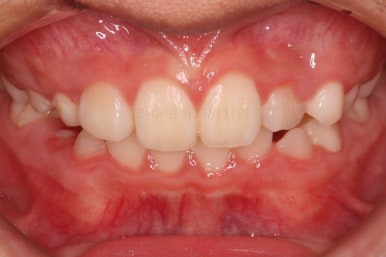

유지단계 4개월째의 모습입니다.

거꾸로 물리는 반대교합이 재발되지 않고 자리를 잘 잡고 있습니다.

위턱뼈가 넓어지다보니 처음에는 삐뚤었던 앞니도 자연스레 자리를 잡아가고 있습니다.